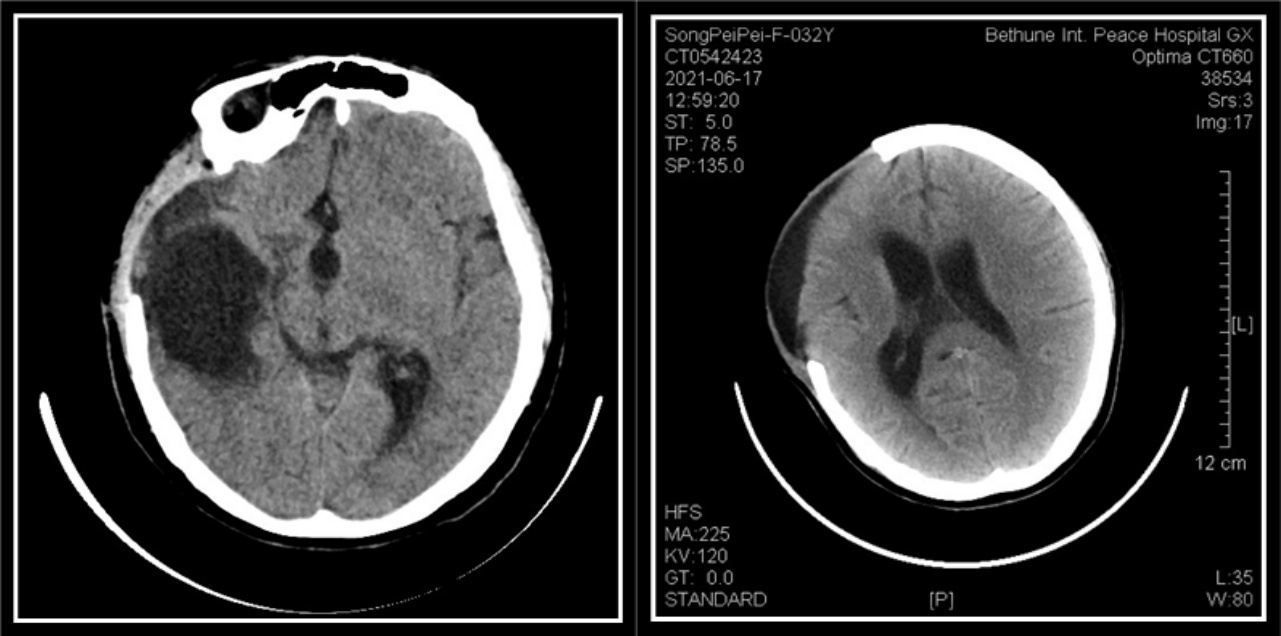

術后1月